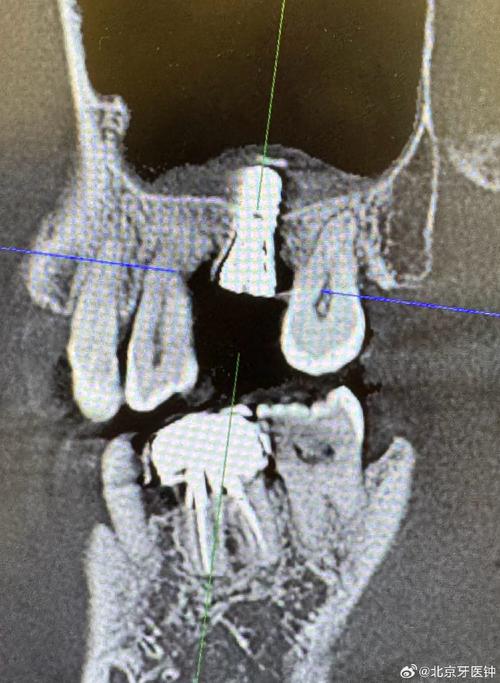

上颌窦是位于上颌骨体内的空腔,与鼻腔相通,由一层薄薄的骨壁(上颌窦底壁)与牙槽骨相隔,当后牙缺失后,牙槽骨会因失去功能性刺激而逐渐吸收,尤其是上颌窦底壁处的牙槽骨,吸收后可能导致骨高度不足(通常种植体需要至少5-10mm的骨高度),若直接在骨量不足的区域种植,种植体可能穿透上颌窦底,引发鼻窦感染、出血、种植体松动等风险,甚至导致手术失败,解决上颌窦区域的骨量不足,是上颌后牙区种植成功的关键。

上颌窦提升术,又称上颌窦底骨增量术,是通过外科手术增加上颌窦底骨高度,从而为种植体提供足够骨支持的技术,根据手术方式和骨增量程度,主要分为两类:上颌窦内提升术和上颌窦外提升术。

适用情况:适用于牙槽骨高度轻度不足(4-6mm),且上颌窦底骨壁较厚(≥2mm)的患者,此时骨量虽不足以直接种植,但通过将上颌窦底黏膜向上“顶起”,可在局部植入骨粉,增加骨高度。

适用情况:适用于牙槽骨高度严重不足(<4mm),或上颌窦底骨壁较薄、存在明显凹陷的患者,需通过开窗进入上颌窦窦腔,在黏膜下大量植骨,实现骨量的显著增加。